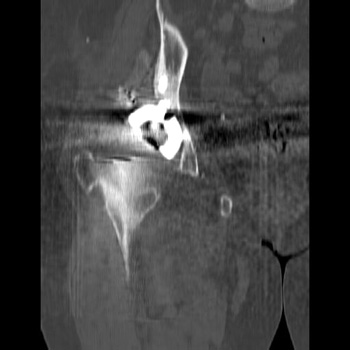

Dislocated femoral component and acetabular cup in grossly loose arthroplasty.  CT guided aspiration to rule out infection.